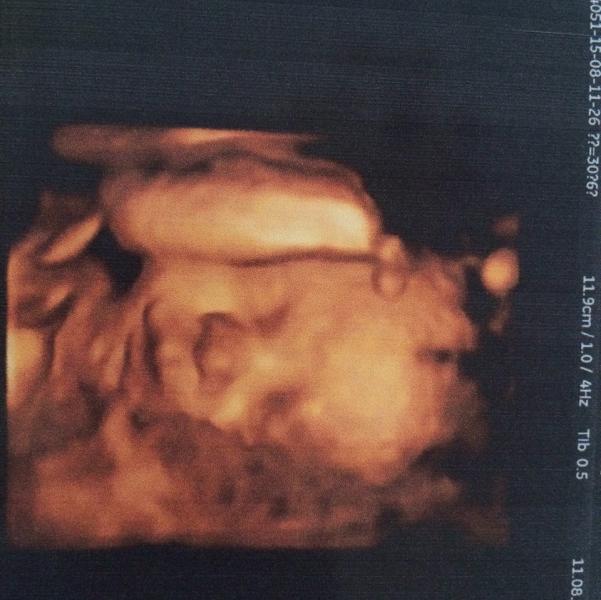

Наше первое фото 😍 вчера виделись с моим сыночком

@chitushkin, вчера, получается 31 неделя

это на каком сроке фото

Сколько весили ваши малыши в 30-31 неделю?

@paty_makeupizb, ой а нам рост не сказали, мы тож 2кг 😊

@renata16, мой на этом сроке 2 кг и 44 см🙈